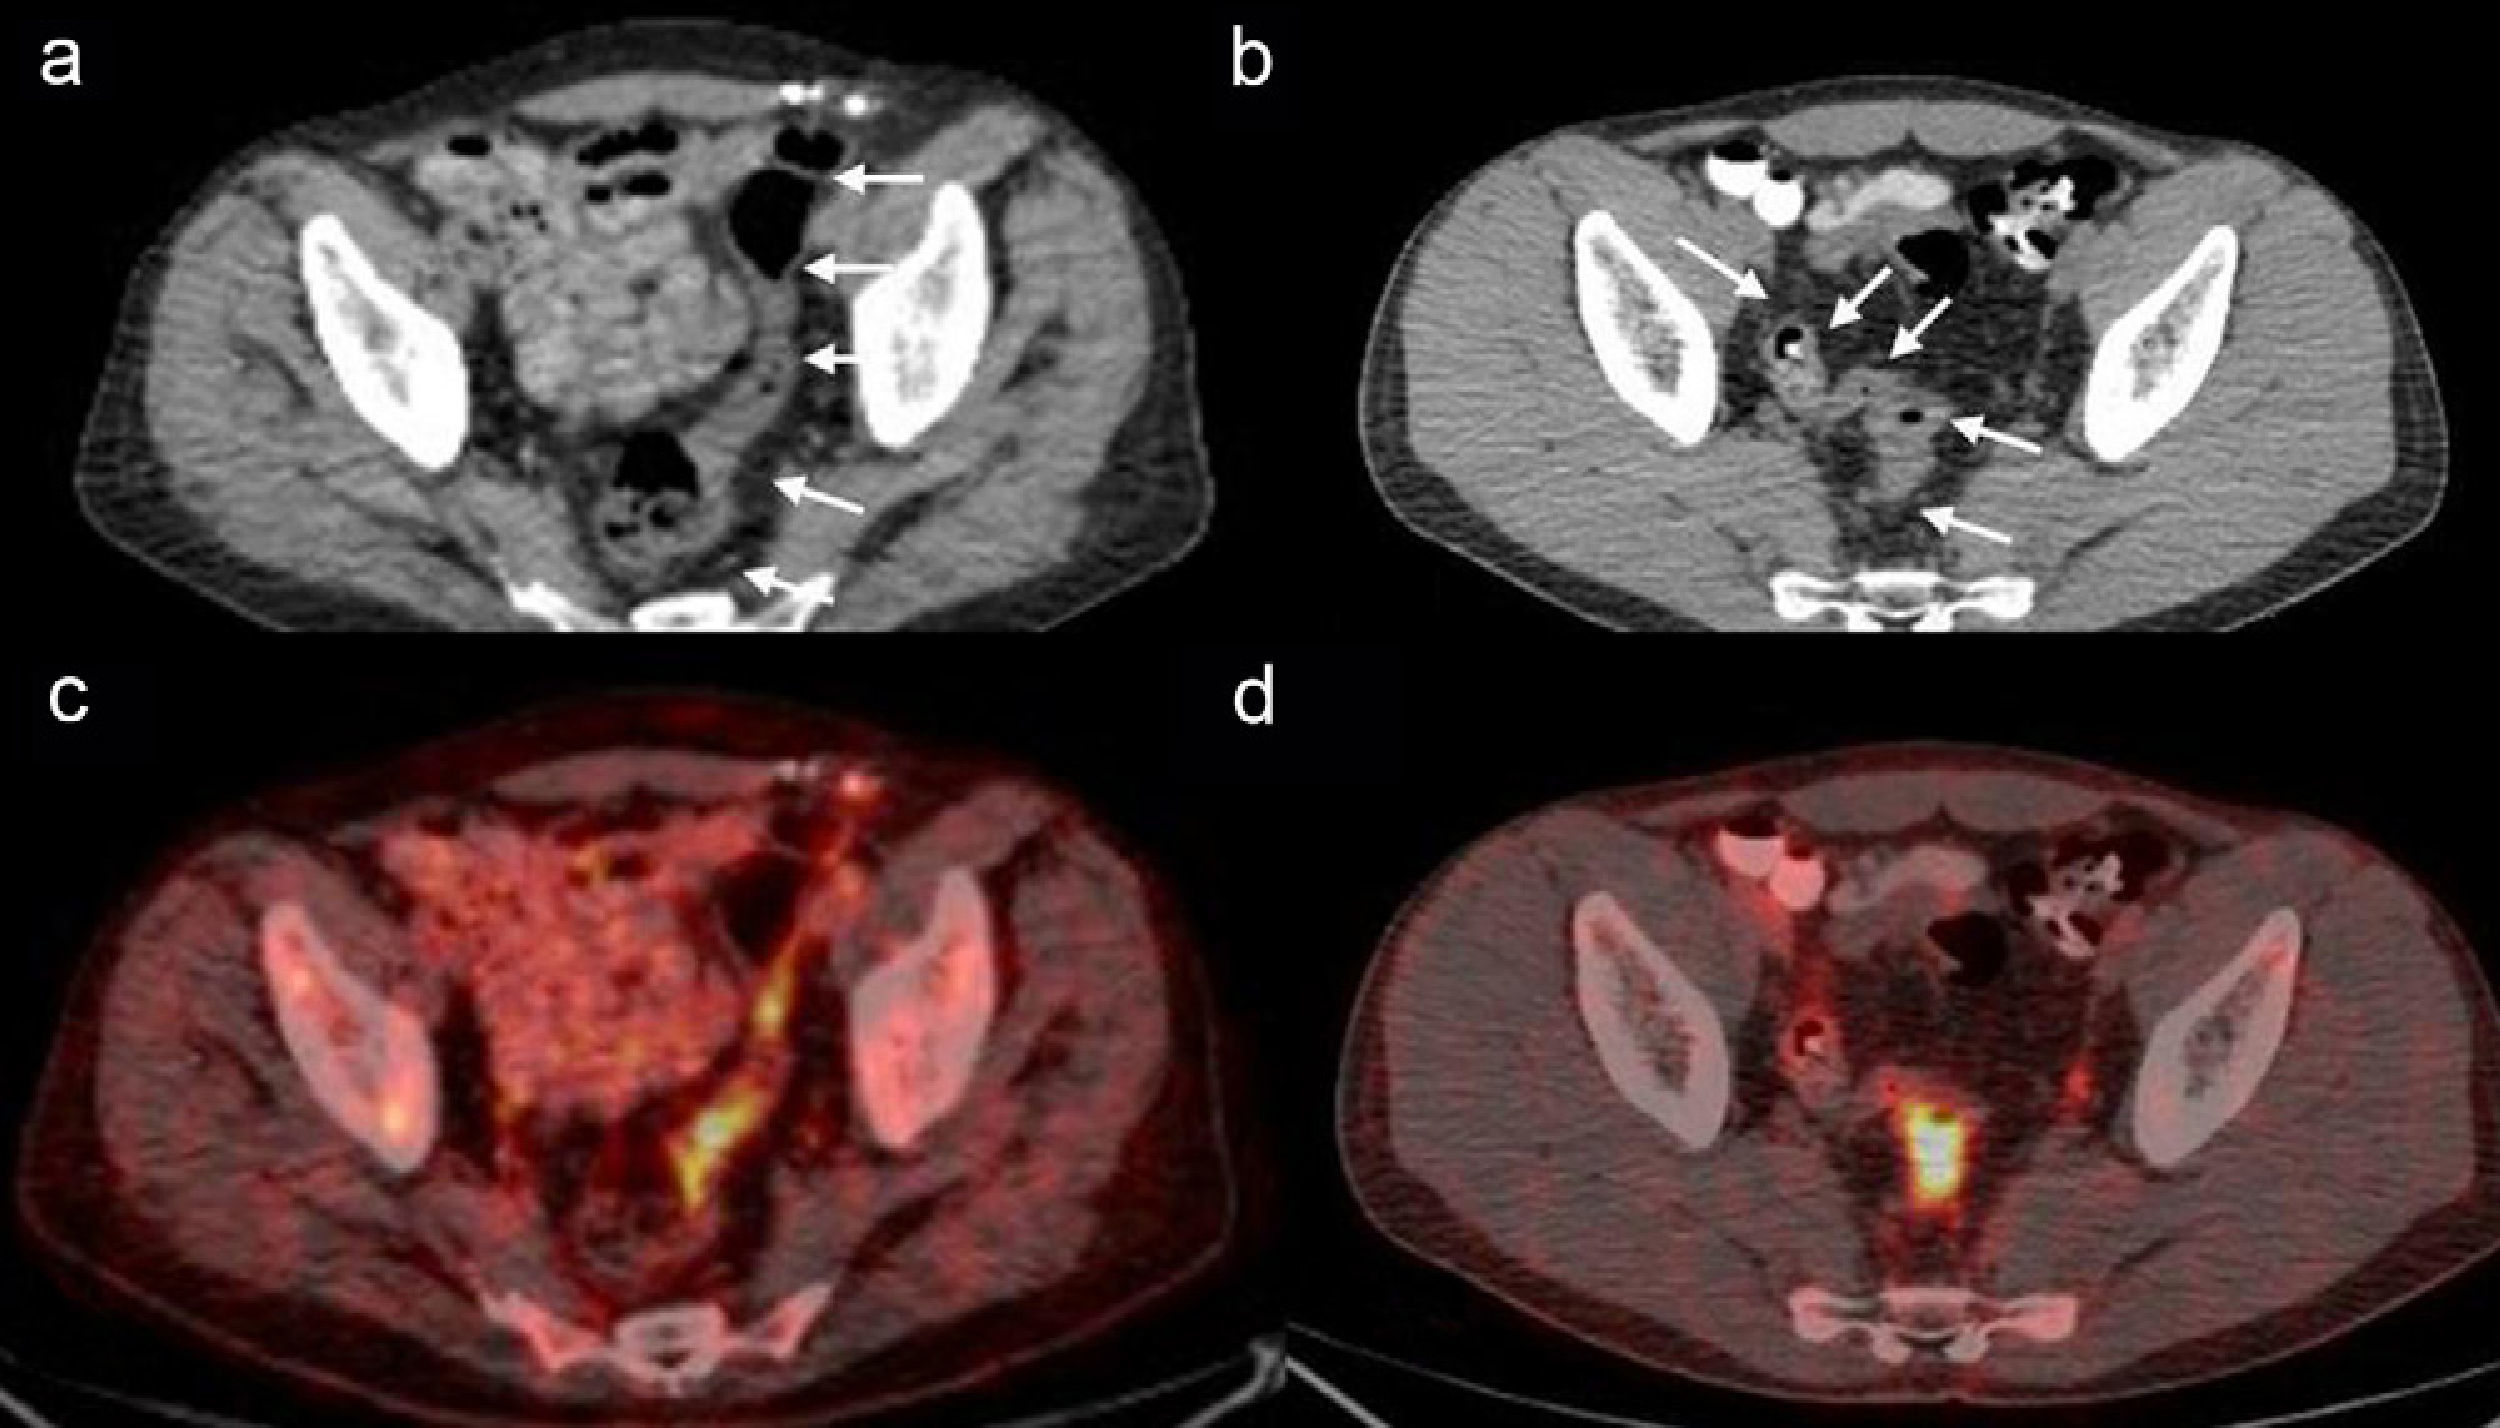

Materials and methodsGastrointestinal tract (GIT) sections of 823 FDG positron emission tomography/computed tomography (FDG-PET/CT) performed in our center were reviewed retrospectively. Images of these cases that have been reported for positive intestinal focal FDG uptake areas were included. Through the sectional images, any accompanying short segment expanded with air just after or before the uptake area was marked as “positive peristaltism sign”. The cases were confirmed with endoscopy plus biopsy (n:42), endoscopy (n:5), laparotomy (n:1), transabdominal biopsy (n:1), enteroclysis (n:1), CT-colonoscopy (n:5), rectal contrast enhanced CT (n:4). Distinguishing features of the sign were analyzed statistically compared to the conventional method for differentiation of malignity.

ResultsLocalized FDG uptake was reported in 59 of 823 cases. A SUVmax greater than 2.5 with intestinal wall thickening allowed the diagnosis of malignity with sensitivity 33%, specificity 65%, positive predictive value 69% and negative predictive value 46%. The peristaltic segment sign, considered as a benign finding, increased the statistical values to 68%, 80%, 82% and 65%, respectively.

ConclusionIn case of gastrointestinal increased focal FDG uptake, the new parameter of peristaltic segment sign may differentiate the physiologic uptakes from the malignant ones more accurately than the conventional SUVmax.